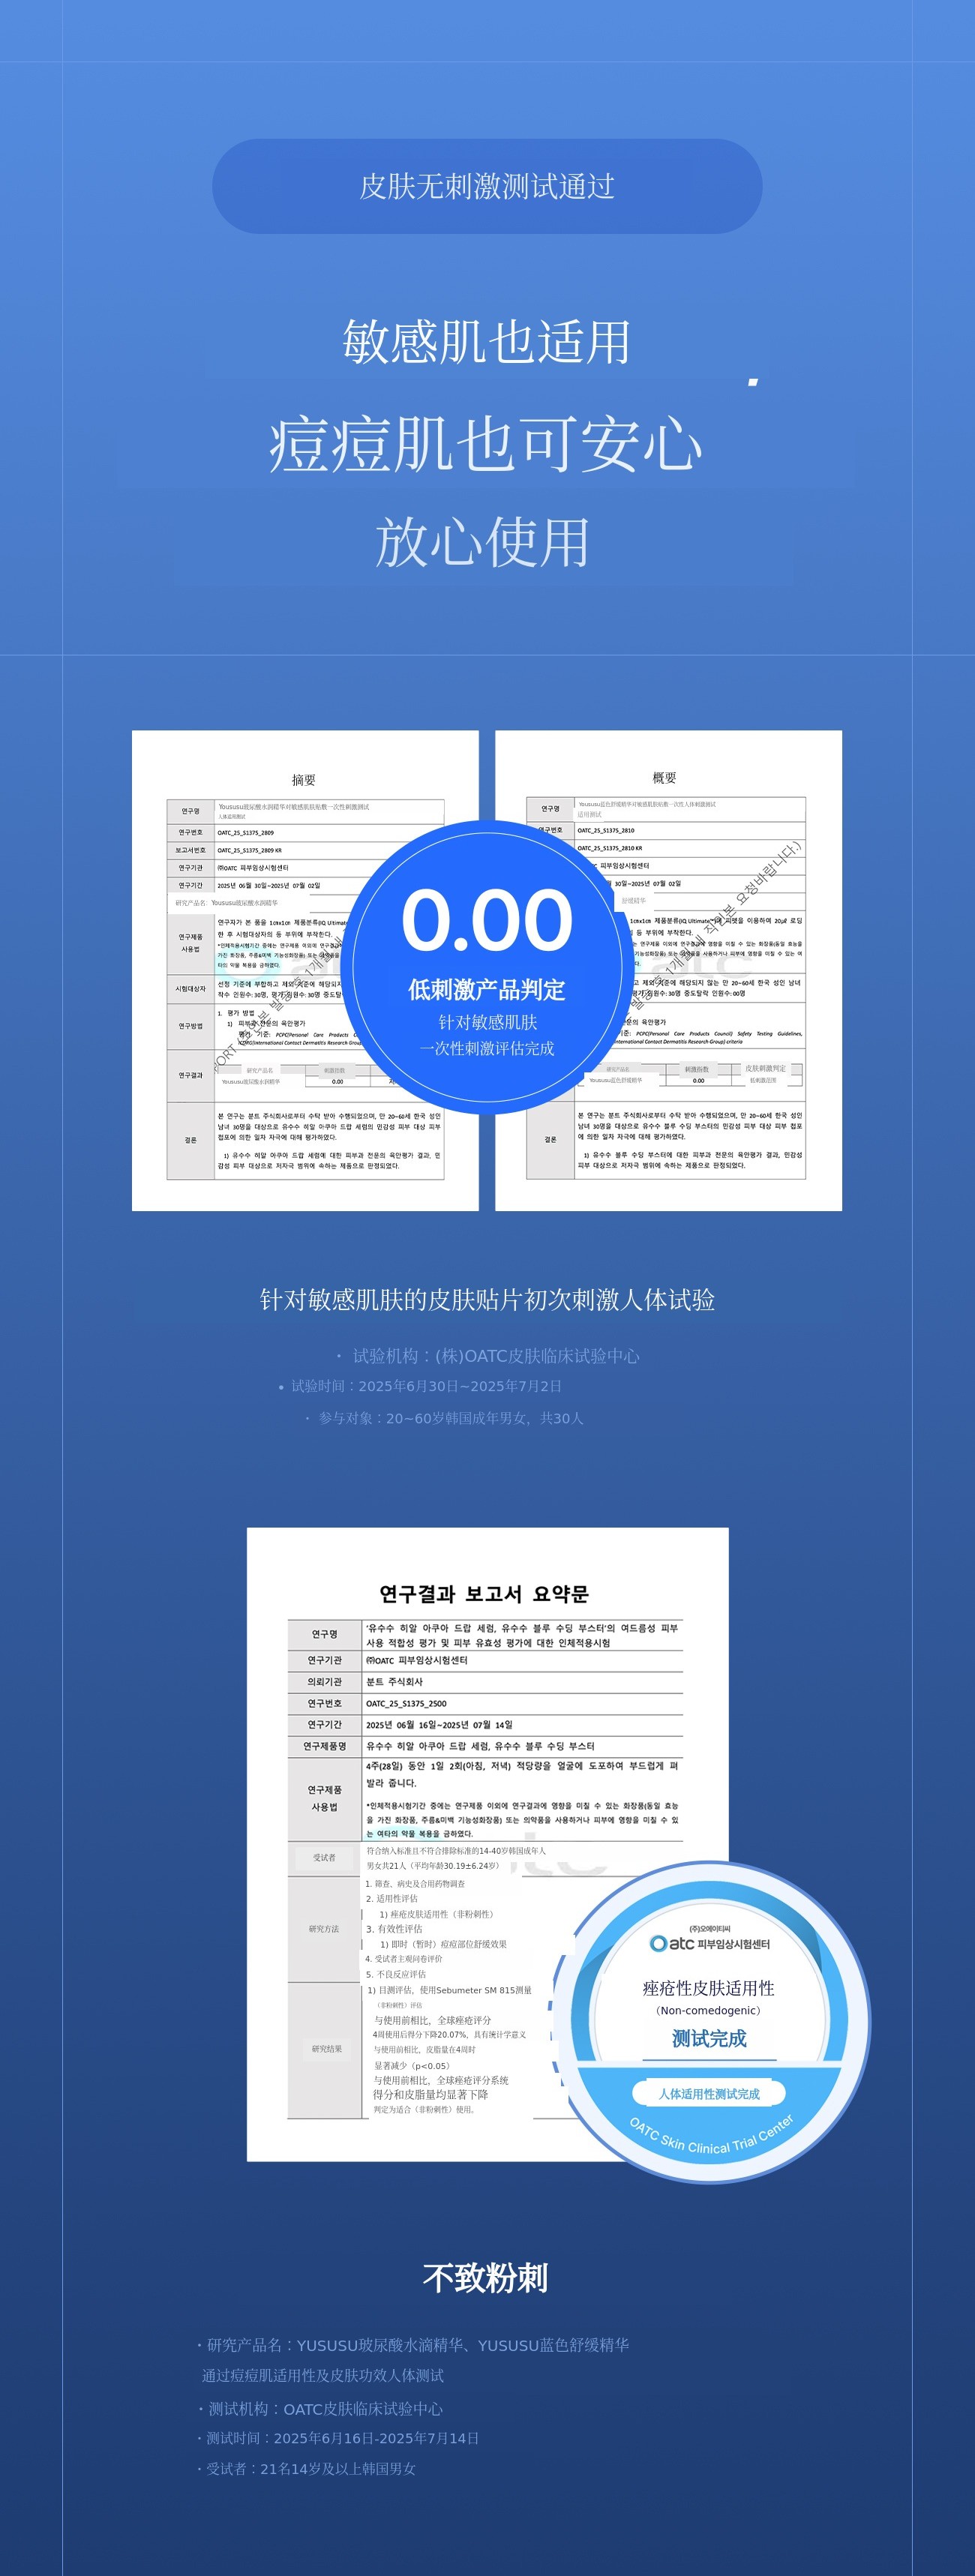

Q3. 痘痘肌、敏感肌也可以使用吗?

A. 可以!Yususu已完成无致痘性测试及敏感肌肤低刺激测试。 不含致痘成分,专为镇静设计,可安心使用。